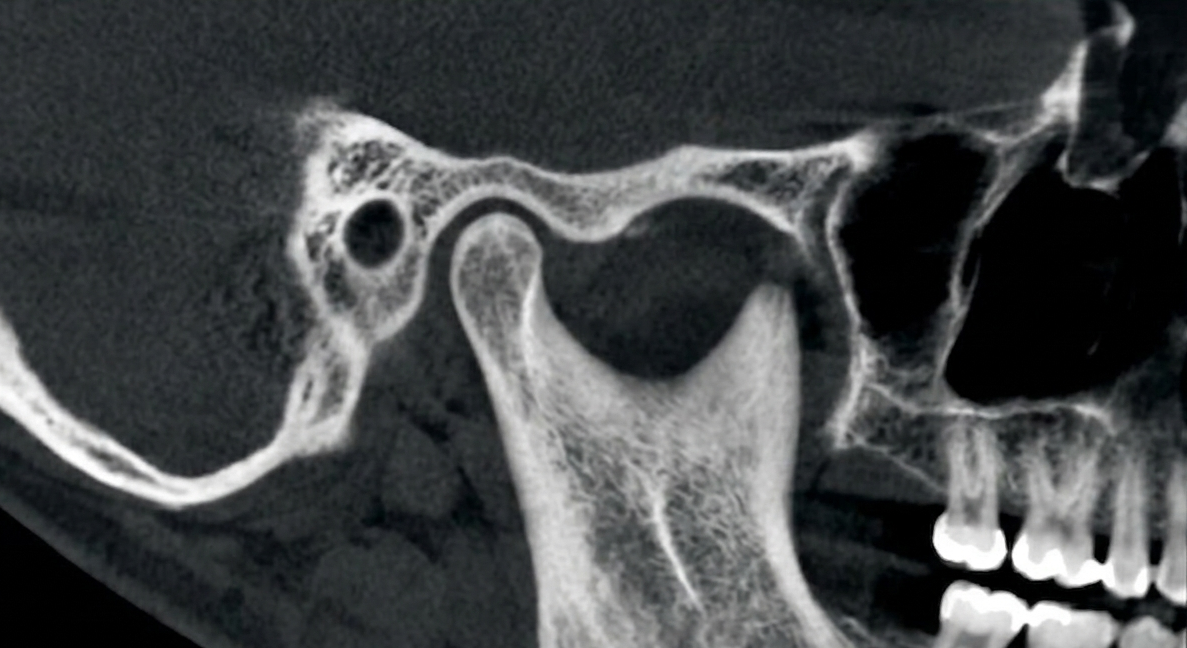

Temporomandibular Joint

Dysfunction (TMD)

tmj evaluation